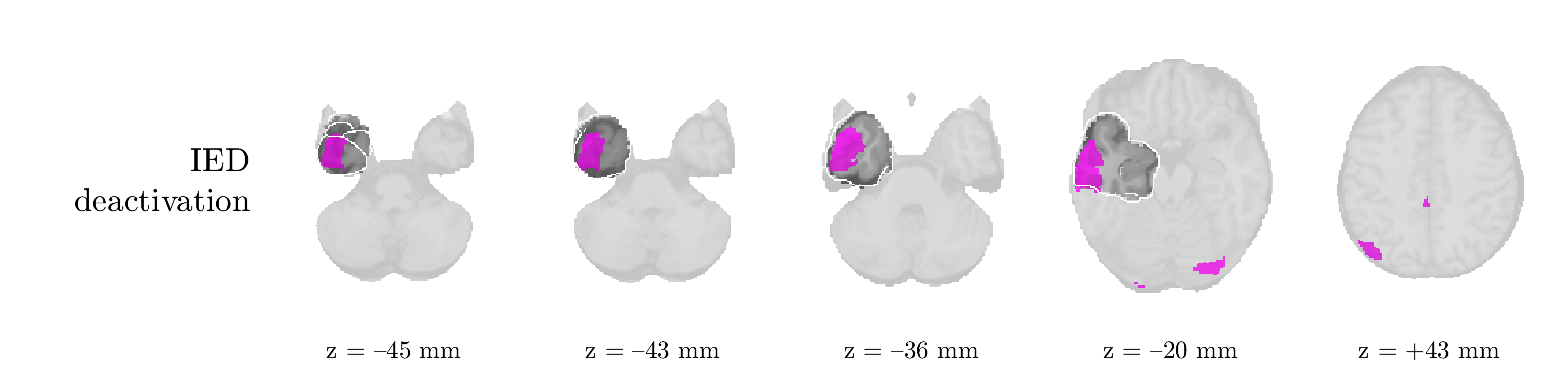

Patient 1

We analyze the solution with sources. Figure 1 shows the EEG signatures and HRF waveforms. One of the sources is highly correlated to the MWF reference (in grey), which was already known from Table B.3. This IED-related source had a typical low-frequency spectrum, which is expected for the typical spike-and-wave interictal discharges. The topography is relatively diffuse, although the highest amplitudes are mostly in the left hemisphere. This is in accordance with the lateralization of ictal onset zone (left temporal lobe, cfr. Table 1). There are some noteworthy observations to be made about some of the other components. The fourth has an unusually sharp spectrum, is mainly localized on two nonadjacent center electrodes, and is sustained for a single period of many seconds Hence, this component likely captured an artifact (of yet unknown origin), although we spotted no large-amplitude changes in the EEG itself. Similarly, the third source is only present at one frontal electrode, and exists in a frequency range above 20 Hz. It might represent a muscle artifact, e.g., due to frowning or twitching of some muscles in the forehead. The HRFs of all ROIs are shown in Figure 1(b). Two of the basis functions seem to have converged to a very similar waveform, which is an unfortunate possibility if two initial HRFs are too close to the same local optimum in their respective parameters. This reduces the expressive power of the basis set, which is clearly visible, since many ROIs have a nearly identical HRF. One of the twenty ROIs with the highest-entropy HRF overlapped the IOZ, although clearly this HRF (bold line) is not among the most dissimilar waveforms for this patient. This is also visible in Figure 2: both the HRF entropy and extremity maps show a small overlap with the delineated IOZ. Despite the good correspondence in the EEG domain, no significant (de)activation of the IED-component is found inside the IOZ.

Patient 2

We analyze the solution with sources, and show the results in Figure 3 and 4. As for patient 1, we found a source which is strongly correlated to the MWF envelope, and which had a mostly low-frequency behavior characteristic for spikes. The topography is mostly uninformative, and does not clearly correspond to the patient’s clinical data. The third source is mostly present at both sides of the head, is very sparsely active in time, and has a high-frequency content: this is most likely an artifact due to the neck muscles. Again, there is one of the highest-entropy HRFs which belongs to a ROI in the IOZ. Now, the waveform is clearly resolved from the other HRFs, through the strong initial dip (before 0 seconds). Such a dip is sometimes observed in HRFs, but its underlying physiological mechanism is not yet fully understood. It is possible that this dip reflects altered vascular autoregulation near the IOZ (cfr. the explanation in the Section 1 of the main text), or a rapid depletion in oxygen due to IED generation (before the IED becomes visible on the EEG). Figure 4 furthermore shows that the IED-related component is significantly active in parts of the IOZ, and deactive in others. As mentioned earlier, this deactivation may or may not be due to errors in sign correction. Interestingly, the ROI with the high alteration in neurovascular coupling is distinct from both the activated and deactivated ROIs.

Patient 4

We analyzed the solution with sources, and show the results in Figure 5 and 6. There is one source which is mostly correlated to the reference (but not extremely, see also Table B.3). This source had a right-temporal focus, conform the diagnosis in Table 1. The second source illustrates the phenomenon of an erroneous sign exchange between the spatial and spectral profiles. Also one of the HRFs has a negative polarity, which is a failure of the sign correction procedure (in this case, because there is exceptionally no positive overshoot). However, the HRF variability metrics are still interpretable, and indeed two ROIs among the ones with the highest-entropy HRFs overlap with the IOZ. The IED component is significantly active in a tiny portion of the IOZ (cfr. Figure 6). The second source is significantly active in symmetrical parts of the parietal lobe. Given its ongoing fluctuation over time, we hypothesize that this source captures a resting state network (RSN).